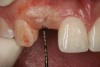

Figure 4  Characterization of the interproximal bone and tooth contacts: A periapical radiograph assists in measuring the distance from bone crest to the adjacent tooth contact points for missing tooth No. 8. The mesial bone crest to the adjacent tooth contact distance is < 5 mm, while the distal bone crest to adjacent tooth contact distance is > 6 mm (Fig 4). One-year following implant placement, conservation of these dimensions is revealed (Fig 5). The clinical photograph (Fig 6) of the lateral incisor adjacent to tooth No. 8 implant crown demonstrates that the absence of distal interproximal (papilla) fill related to the observed bone crest to contact distance exceeds 6 mm.

Figure 4

Figure 5  Characterization of the interproximal bone and tooth contacts: A periapical radiograph assists in measuring the distance from bone crest to the adjacent tooth contact points for missing tooth No. 8. The mesial bone crest to the adjacent tooth contact distance is < 5 mm, while the distal bone crest to adjacent tooth contact distance is > 6 mm (Fig 4). One-year following implant placement, conservation of these dimensions is revealed (Fig 5). The clinical photograph (Fig 6) of the lateral incisor adjacent to tooth No. 8 implant crown demonstrates that the absence of distal interproximal (papilla) fill related to the observed bone crest to contact distance exceeds 6 mm.

Figure 5

Figure 6  Characterization of the interproximal bone and tooth contacts: A periapical radiograph assists in measuring the distance from bone crest to the adjacent tooth contact points for missing tooth No. 8. The mesial bone crest to the adjacent tooth contact distance is < 5 mm, while the distal bone crest to adjacent tooth contact distance is > 6 mm (Fig 4). One-year following implant placement, conservation of these dimensions is revealed (Fig 5). The clinical photograph (Fig 6) of the lateral incisor adjacent to tooth No. 8 implant crown demonstrates that the absence of distal interproximal (papilla) fill related to the observed bone crest to contact distance exceeds 6 mm.

Figure 6